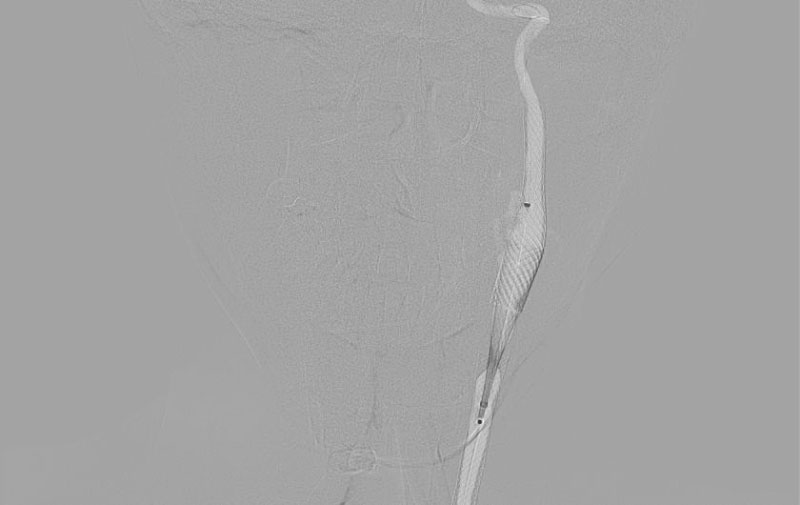

'25年10月

左総頚動脈狭窄症

30代

院内外来

No.1590 手術中